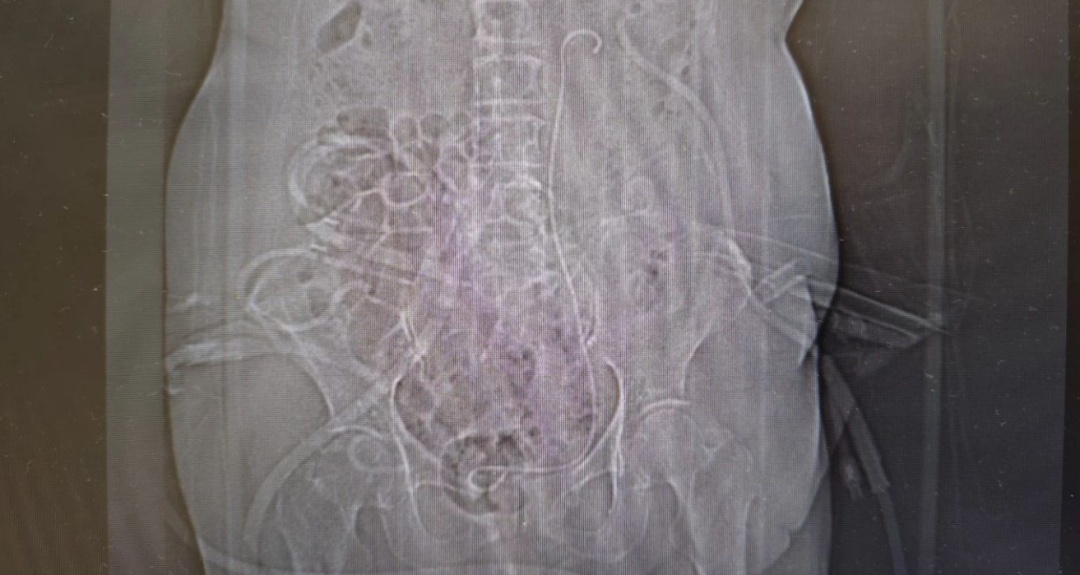

术后腹部平片示结石已完全清除